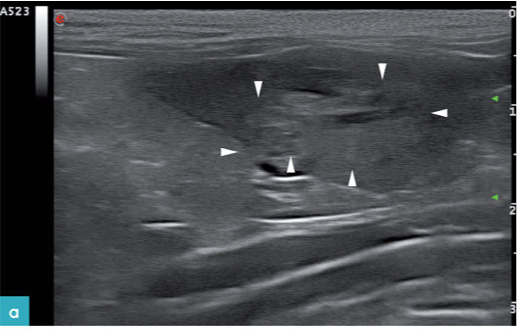

最常见的猫脾脏肿瘤是肥大细胞瘤和淋巴瘤。在一项研究中称,淋巴瘤病例中最常发现的异常就是脾脏肿大。发生肿瘤的脾脏实质有多种回声表现,例如弥散性的低回声点状区域多处小型低回声暗区或独立的低回声团块。在有些病例中,仅发现脾脏实质回声降低但并没有发生脾脏肿大或是仅见独立的脾脏肿块(图9.图3)。同时伴发的症状包括有腹膜腔积液,腹腔淋巴结增大及肝脏病变。

对27只患有脾脏肥大细胞瘤的猫进行研究,观察这些猫的脾脏影像,发现与患有淋巴瘤的病变影像相似。在这些病例中,93%的猫都有不同程度的脾脏肿大,其中有6只猫唯一的异常表现就是脾脏肿大。在2只缺乏典型症状的猫的检查中仅发现有脾脏增大,且有多处高回声的结节。其中1只猫的脾脏呈广泛性高回声,同时伴有脾脏肿大。在其中7只猫的脾脏上发现有单独的结节或肿块(图10.图4)。30%的猫同时伴有肝脏的变化。33%的猫有腹膜腔积液。

患有内脏型肥大细胞瘤的猫,它的副肿瘤综合征表现为胸膜腔和腹膜腔的渗出液中含有嗜酸性粒细胞,同时外周血中也含有较多的嗜酸性粒细胞。然而,这项研究没有发现能够区分肥大细胞瘤和淋巴瘤的超声特征。但是通过这项研究发现,患有淋巴瘤的猫发生腹腔积液的概率比肥大细胞的患猫高(47%比33%),发生肠系膜或腹膜后淋巴结病变概率也比肥大细胞的患猫高(37%比3%)。肥大细胞瘤的患猫脾脏的轮廓则更为不规则,并且高回声病灶仅见于肥大细胞瘤的患猫。这表明小型的高回声结节或弥漫性高回声结节虽是比较少见,但如果发生,可以作为猫脾脏肥大细胞瘤的特异性影像。